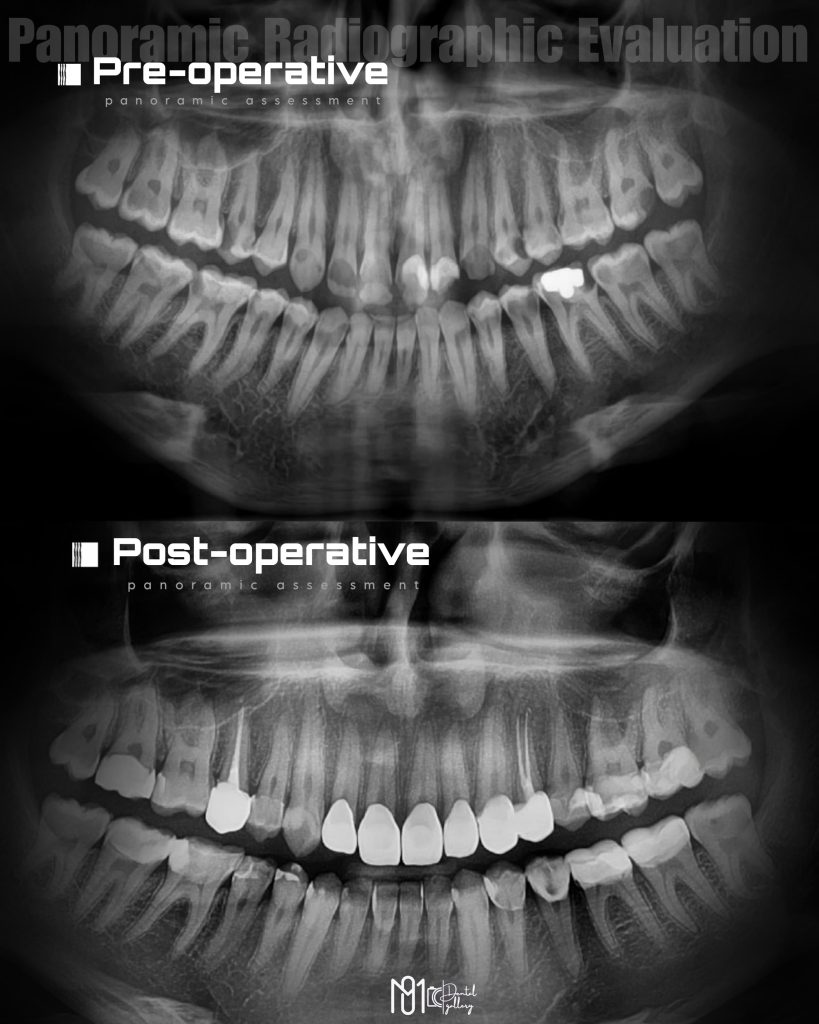

Proud to finally share my Comprehensive Clinical Care (CCC) case — a full-mouth rehabilitation journey that truly tested my skills, patience, and dedication.

The case involved managing extensive carious lesions across both arches, performing root canal treatments, direct and indirect restorations, and even a periodontal surgical procedure.

I treated multiple deep caries cases using Immediate Dentin Sealing (IDS), performed Composite Resin Restorations (CRR) for both anterior and posterior teeth, and placed temporary restorations to maintain occlusion before the final prostheses.

In total, this case included 23 composite restorations, 7 full coverage crowns, and 2 root canal treatments, all completed between February 10th, 2025 and May 12th, 2025.

The case was then followed up for 5 months, up until September 23rd, 2025, ensuring long-term stability and success.